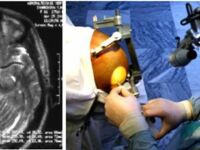

Клиника входит в число ведущих научно-практических центров России, располагает 100 койками, ежегодно выполняется до 1500 операций высшей категории сложности с результатами, сопоставимыми с ведущими европейскими клиниками.

Виды медико-хирургической помощи